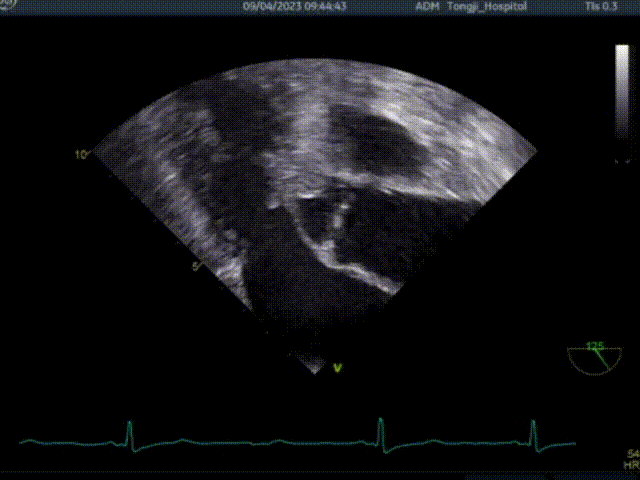

术前超声TEE检查结论:

1. 左室非对称性肥厚,左室流出道梗阻,二尖瓣重度关团不全;

2. 二尖期后叶脱垂;

3. 卵圆孔未闭(极细缝隙)。

患者术前大量反流,前叶SAM征,室间隔增厚最厚处13mm